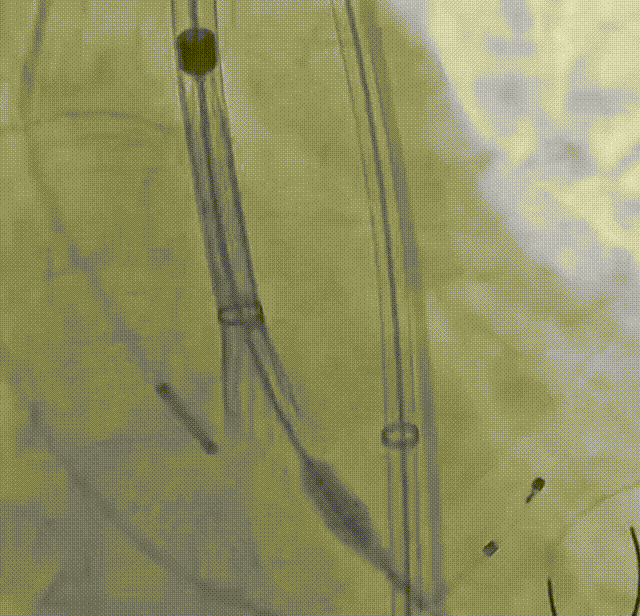

罗建方教授 广东省人民医院(点击查看专家详细简历) 设计本为临床需,耐久守护好芳华:任何医疗产品的设计初衷与最终归宿,都应落在 “临床获益” 这一核心上。尤其在 TAVR 领域,年轻患者预期寿命长,术后瓣膜的长期性能直接关乎其生活质量与生存预后。瓣膜耐久性问题,是落到临床实践中亟待突破的关键课题。传统瓣膜在长期使用中,可能因结构老化、功能退化等问题,难以满足年轻群体数十年的健康需求,二次手术风险也随之攀升。因此,产品设计必须直面这一临床痛点:通过材料革新增强抗钙化性能及生物相容性,以技术突破延长瓣膜有效使用寿命。此次临床应用的预装干瓣Prostyle A®是TAVR领域的革新理念,干瓣预期会为临床提供更耐久性的保障,实现了与临床需求的精准对接,为年轻群体的瓣膜治疗提供更坚实的保障。 李捷教授 广东省人民医院(点击查看专家详细简历) 干瓣技术求革新,性能兼顾护临床:干瓣的技术革新在创新的同时需要和临床实际需求深度耦合,兼顾TAVR术中的核心考量点。临床操作中,瓣膜能否顺利过弓,直接影响手术效率与安全性。Prostyle A®短瓣架设计及第二台阶的柔顺设计,术中操作丝滑;同时,瓣膜植入后的径向支撑力必须平衡得当,才能实现稳定锚定;释放后造影显示:瓣膜形态舒展,轻度瓣周漏,舒张压升高,冠脉开口未受影响;瓣周漏是影响术后效果的关键隐患,双层裙边设计通过多重密封机制降低反流风险,为患者长期获益筑牢防线。这些性能的协同优化,最终目的是让干瓣在临床中真正做到 “好用、耐用、安全用”,为患者预后提升提供坚实支撑。 患者病史 患者因 “活动后气促伴头晕 2 月” 入院。 现病史:2月前无诱因出现活动后气促,休息后缓解,伴头晕,夜间阵发性呼吸困难。超声检查发现:主动脉瓣重度狭窄并重度返流(跨瓣流速 4.3m/s,峰值压差 73mmHg);主动脉 + 冠状动脉 CTA 提示主动脉瓣显著钙化,升主动脉及分支粥样硬化,冠状动脉轻度狭窄(RCA 狭窄 30-40%)。 既往史:高血压病史 15 年,规律服药,血压控制稳定。 术前诊断:非风湿性主动脉瓣狭窄伴关闭不全(重度)、心功能 II 级(NYHA)、高血压病 2 级(高危)、冠状动脉粥样硬化。 术前CT 三叶瓣,瓣叶增厚中度钙化,右无交界钙化粘连,瓣环径25.1mm,LVOT 25.1mm,直筒型结构;窦部空间足够,升主未见增宽,瓣环水平夹角55°;冠脉开口位置佳,无冠脉风险;入路散在钙化、外周双侧入路无明显迂曲,双侧内径可、中分叉,左右侧均能够支持20F 大鞘通过。 造影角度及入路 右窦居中位RAO 5° CAU 26° 左冠切线位LAO 11° CRA 12° 手术策略 右侧股动脉为主入路,左侧为辅助入路;使用20球囊预扩,准备AV26瓣膜,冲洗口朝向3点钟方向送入输送系统性能,初始定位真实瓣环0位释放,最终锚定约瓣下3mm,工作位评估瓣膜稳定性与冠脉情况。 手术过程 根部造影 20mm 球囊预扩无明显腰征 术中使用26号瓣膜,瓣膜释放贴边迅速 80% 工作位观察瓣膜位置良好 释放后造影显示:瓣膜形态舒展,轻度瓣周漏,舒张压由术前30mmHg升为 60mmHg,冠脉开口未受影响。 术后超声:跨瓣流速降至1.6m/s,平均压差降至5 mmHg,心功能显著改善。 Prostyle A®预装干瓣——助力临床最优化解决方案: 1. 抗钙化与耐久性:Micro-EX™专利技术提升瓣膜抗钙化能力,适配患者瓣叶中度钙化的解剖特点,为长期疗效提供保障。 2. 柔顺过弓与精准定位:短瓣架设计 + 远端超滑涂层,确保患者输送系统过弓顺畅;瓣架流入端微直筒设计,让定位贴边更迅速,减少了手术时间; 3. 80% 可回收设计:便于术中调整观察,减少起搏时间,从而减少并发症。 4. 简化手术流程:预装设计缩短操作时间,20F 大鞘兼容外周入路,降低血管损伤风险。